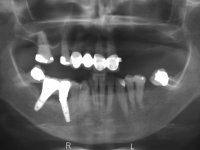

Paciente do sexo feminino, com 69 anos, não fumadora. Apresenta uma prótese combinada no maxilar superior. A porção fixa corresponde a uma ponte metalo-cerâmica de 4 elementos com os dentes 1.3/1.1 e 2.1 como pilares e o dente 1.2 como pôntico. A porção amovível corresponde a uma prótese esquelética de 5 elementos. A retenção da prótese esquelética é feita por um gancho no dente 1.4 e um “attachment tipo t” colocado no dente 2.1.

A reabilitação proposta, consistia na colocação de uma ponte metalo-cerâmica implanto-suportada no 2º quadrante, evitando-se a prótese esquelética. Após a realização do estudo imagiológico, seria decidido definitivamente, o número e localização dos implantes a colocar. A paciente não mostrou interesse na substituição da ponte metalo-cerâmica antero-superior.

O estudo imagiológico para a colocação dos implantes, começou com a realização em laboratório de uma guia com dentes em sulfato de bário. Esta guia foi colocada em boca conjuntamente com marcas de referência coladas aos dentes, também em sulfato de bário. A guia foi estabilizada com cera mole. A TAC foi realizada com estas referências colocadas em boca. Após a realização da TAC foi feita uma impressão de arrasto em silicone. Esta impressão foi vazada a gesso em laboratório e posteriormente digitalizada. A digitalização do modelo com as referências foi sobreposta á imagem da TAC, permitindo uma planificação apurada na colocação dos implantes. Na planificação foi decidido colocar 2 implantes no local dos dentes 2.3 e 2.4 evitando-se a zona do 2.2 com pouco osso e o seio maxilar. Este estudo deu origem a uma guia cirúrgica que orientou a colocação dos implantes. Durante o período de osteo-integração a paciente utilizou a prótese removível rebasada com acondicionador de tecidos. A guia cirúrgica mostrou-se também útil na exposição dos implantes mostrando a sua localização precisa e orientando a incisão. A impressão definitiva foi realizada utilizando a técnica de moldeira aberta após eliminação do attachment. No laboratório foi confeccionada uma ponte metalo-cerâmica de 3 elementos com o elemento 2.2 em suspensão. A ponte após verificação e aprovação foi cimentada. A reabilitação apesar de pouco extensa (sem o elemento 2.6) mostrou-se capaz estetica e funcionalmente.